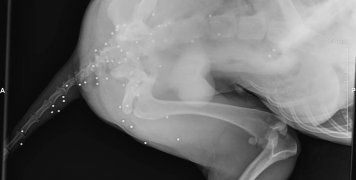

- Πυροβολήθηκε δεσποζόμενος σκύλος στον Κάμπο. Στη φωτογραφία 4 ακτινογραφία όπου διακρίνονται τα σκάγια στο σώμα του.